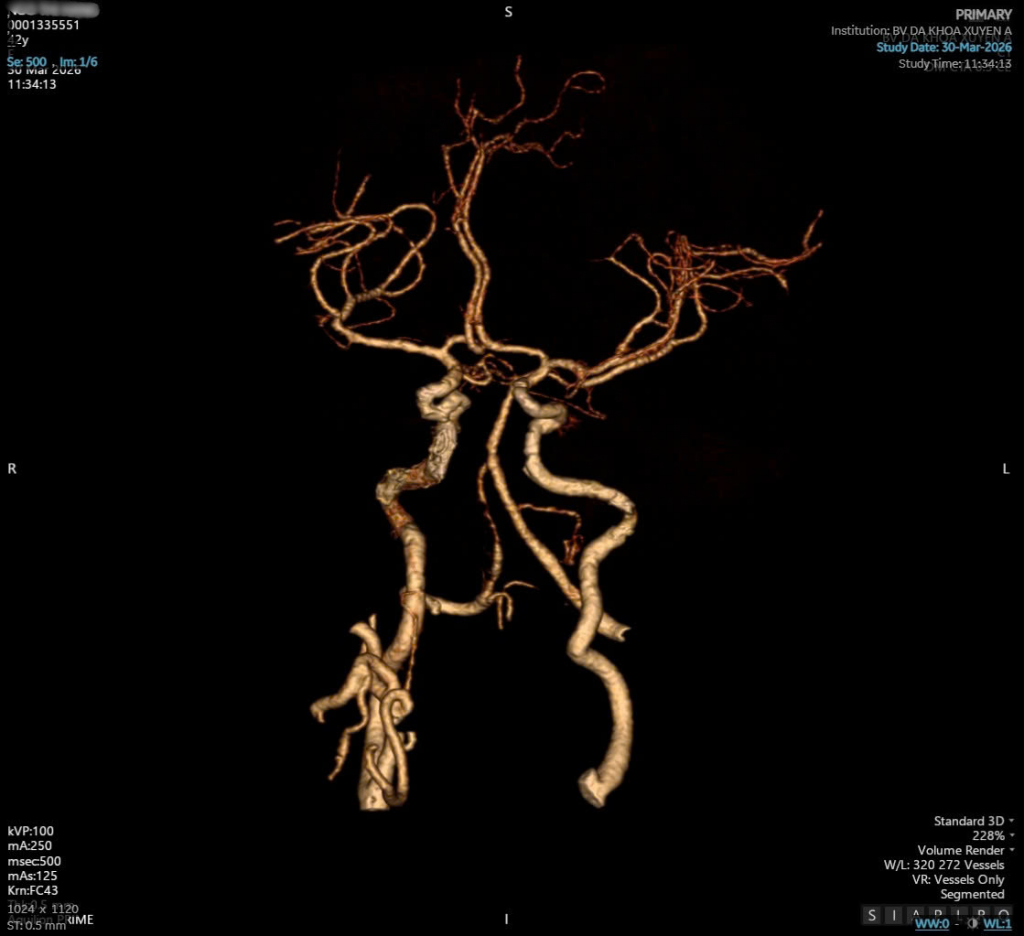

Hình ảnh phim CT bệnh nhân H

Trường hợp thứ ba là một nữ bệnh nhân còn khá trẻ, chị N.T.H (43 tuổi, Tây Ninh). Chị đã mắc tăng huyết áp nhiều năm nhưng không điều trị đều đặn. Chính sự chủ quan này trở thành nguyên nhân dẫn đến cơn đột quỵ cấp. Bệnh nhân nhập viện trong tình trạng tê yếu nửa người bên phải, huyết áp lên đến 220/120mmHg – cao hơn rất nhiều so với mức bình thường. Nhờ được gia đình phát hiện sớm và nhanh chóng đưa đến Bệnh viện Đa khoa Xuyên Á trong “thời gian vàng”, chị đã được điều trị bằng thuốc tiêu sợi huyết kịp thời. Sau điều trị, bệnh nhân hồi phục hoàn toàn: hết tê tay, không còn yếu liệt và không còn chóng mặt.